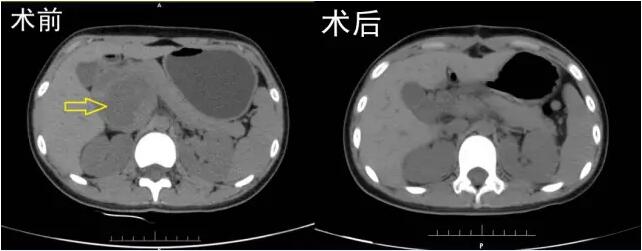

8月2日,手术在紧张有序的气氛中如期进行,术中发现肿瘤体积巨大,6cm×6cm×5cm,起源于胰头,周围与门静脉、胆总管下段及胰管关系密切,其中门静脉及胆总管明显受压并推挤移位,已经严重影响了门静脉血流及胆汁的正常排放。并且门静脉多支粗大侧支血管布满肿瘤表面,手术难度可想而知。在李晓勇主任医师、崔卫东副主任医师、陈升阳医师及张永医师的共同努力下,有麻醉科郭佩垒医师的保驾护航,历经4个小时的奋战,迎难而上,巨大肿瘤被成功切除。此时检查手术创面,发现胆总管下段、门静脉主干完全裸露,因为术中操作精细,这两个重要结构没有任何损伤。至此,手术室里紧张窒息的气氛一下子就缓和了,主任也舒展了眉头。当李主任将切除的肿瘤让莹莹妈妈查看时,莹莹妈妈更是激动地热泪盈眶。

手术前后对比

术后经过精心的治疗及护理,患者恢复顺利,3天后开始进食,1周顺利出院。出院时,患者父母喜悦及感激的心情无以言表,特地制作了一副沉甸甸的金匾,借此再次向李晓勇主任及科室全体医务人员表达深深的谢意。